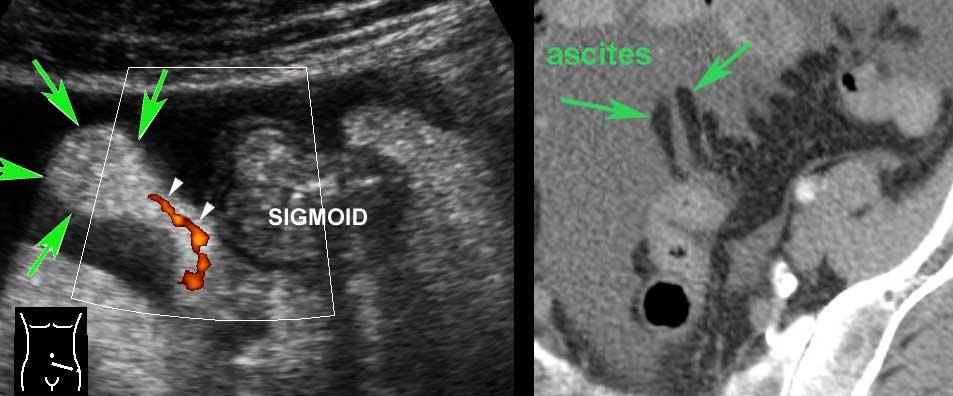

Lớp thanh mạc trắng bên ngoài chỉ có thể được xác định khi có cổ trướng.

Nếu có dịch trong ổ phúc mạc, lớp thanh mạc tăng âm (mũi tên) có thể được nhận diện riêng biệt, như trong các quai hồi tràng này.

Mạc treo bình thường (mũi tên) ở những bệnh nhân gầy chỉ có thể nhìn thấy khi có cổ trướng.

Hình ảnh dọc (trái) và ngang (phải) của đại tràng sigma rỗng ở bệnh nhân gầy.

Trong hình ảnh mặt cắt ngang, ba vùng dày lên cục bộ của lớp cơ (đầu mũi tên) đại diện cho ba dải cơ dọc kết tràng (đầu mũi tên).

Đại tràng bình thường chứa đầy phân (trái), trong quá trình co thắt (giữa) và trong quá trình giãn và nén (phải).

Normal colon wall thickness during compression is 3-4 mms.

Bóng lưng âm học của phân cản trở việc hiển thị siêu âm thành sau (bên trái).

Đại tràng được phân biệt với ruột non bởi vị trí, nội dung phân, nhu động thưa và lớp cơ ngoài dày với ba dải cơ dọc (tenia coli).

Lớp cơ của đại tràng sigma có thể thay đổi đáng kể về độ dày, chủ yếu do sự co bóp.

Sự dày lên vĩnh viễn của lớp cơ có liên quan đến sự phát triển của các túi thừa (mũi tên).

Sigmoid diverticulosis in four different patients.

Các túi thừa chứa đầy phân được quan sát rõ nhất khi đại tràng co lại.

Chúng biểu hiện là các cấu trúc phản âm sáng với bóng cản âm ở bờ ngoài của đại tràng.

Lưu ý độ dày thay đổi của lớp cơ ở bốn bệnh nhân này.